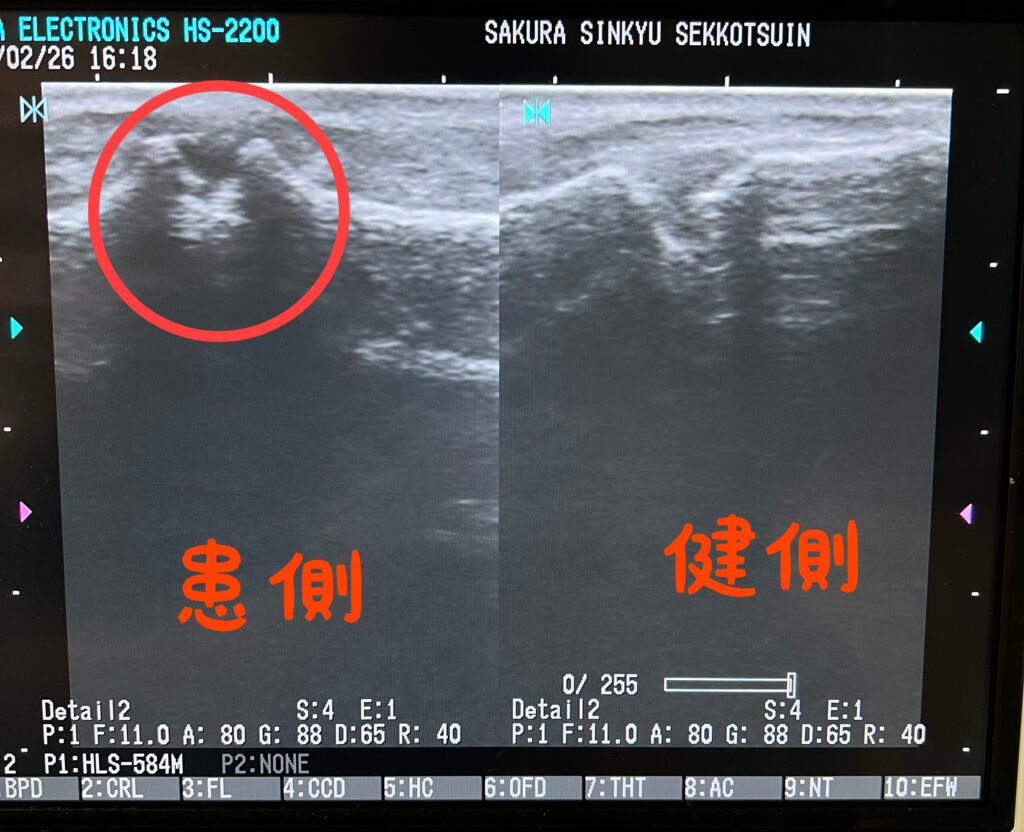

【その足の痛み、“リスフラン関節の変形”が関係しているかもしれません】 リスフラン関節の変形による痛みで当院に来院された患者さんの様子です。

このような症状がある方は、 **リスフラン関節(足根中足関節)の機能低下や変形**が関与している可能性があります。

リスフラン関節とは、足の甲にある関節で、 “体重を支える・力を伝える”という重要な役割を担っています。

この関節が不安定になったり、アライメントが崩れることで 足部全体のバランスが乱れ、痛みや機能障害が出現します。